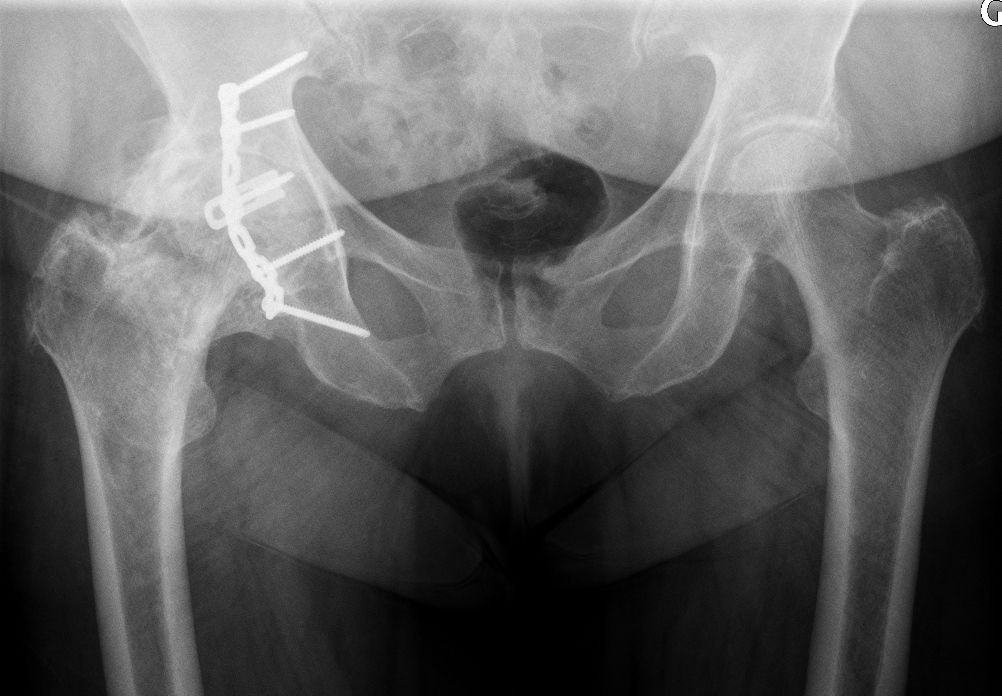

Given the single neck diameter of most femoral stem designs, the head–neck ratio increases proportionally with the head diameter. Theoretically and clinically, this leads to a greater hip range of motion [18,19]. In addition, due to a supraphysiological arc of motion, extraarticular impingement is the first to occur whilst inter-component impingement is rare. Consequently, less-than-optimal implant positioning can be much better tolerated[20]. This is an important point considering the extent of surgical indications for patients with primary or secondary anatomical deformations (e.g. dysplasia, acetabular retroversion, previous pelvic osteotomy, post traumatic), because achieving an optimal implant position is often challenging (Fig. 7).

The relationship between the spine, pelvis and hip was recently recognized as a very important factor of component impingement, limited ROM, and instability after THA with standard bearing diameters[21–26]. There is an unarguable benefit to considering static and dynamic spinopelvic parameters, which will surely become an integral part of preoperative planning. However, despite scientific interest, this has rather limited use in daily practice. Being able to apply the recommendations for a functional implant alignment requires sophisticated preoperative 3D imaging techniques and precision intraoperative tools if the surgeon is to adhere to the preoperative plan (precise acetabular component orientation +/- 2–5 degrees). Being a forgiving implant, an LDH THA is a much simpler solution. The supraphysiological ROM offered by the large head–neck offset can compensate for abnormal spinopelvic mobility and the surgeon’s imprecision. Furthermore, over a lifetime, spinopelvic mobility and parameters may change. LDH THA should be able to accommodate these unpredictable changes. When implanting an LDH acetabular component, our goal is to obtain functional alignment of the bearing (congruency between the femoral head and the acetabular component) with the hip in 10–20° flexion, 10° adduction and 20–30° internal rotation. This is the modified Ranawat’s sign as published by Thomas J. Blumenfeld[27].